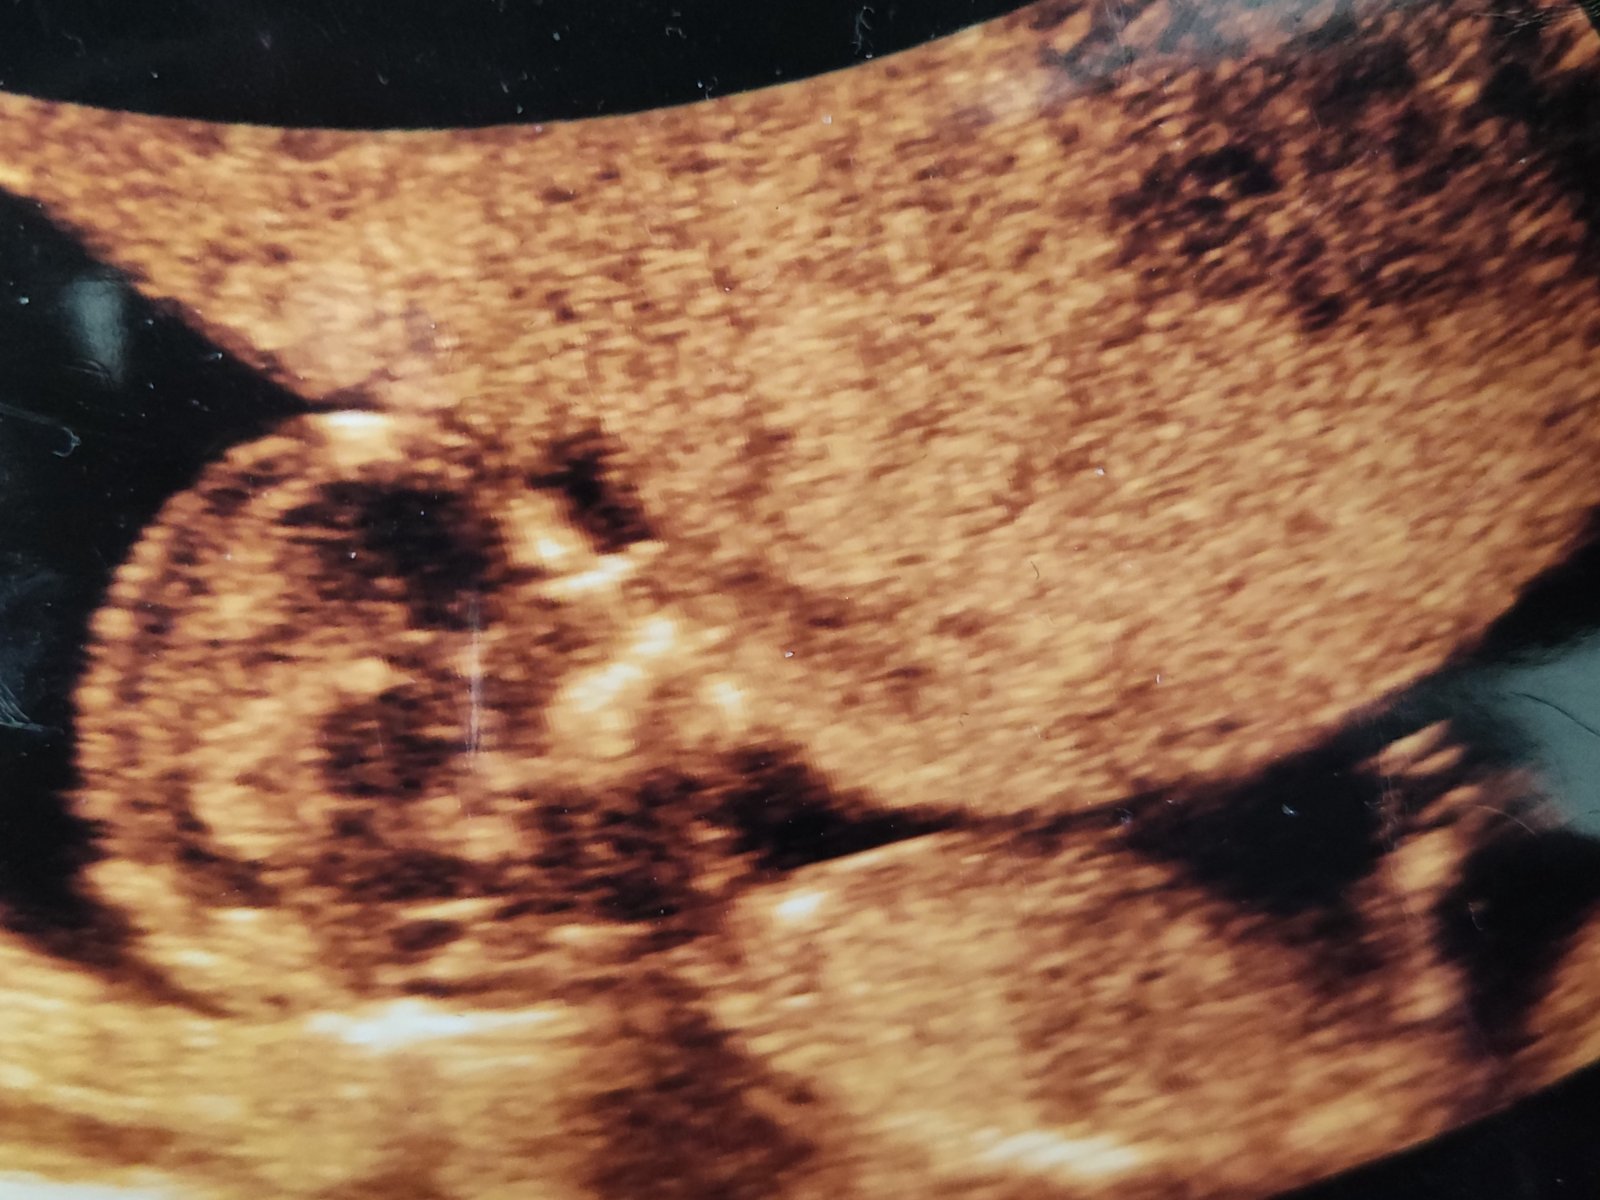

Holky, já se z dovolením přidám. Co by jste si troufly rici, že to je chlapecek nebo holcicika? Doktorka na screeningu rikala na 70% kluk. Mam doma už dva, a prostě vůbec se mi tomu nechce věřit, že se té holčičky už nedočkam 😞😀🙏🏻🙏🏻 Kazdopadne jsme radi, ze je miminko zdrave 🩵🙏🏻